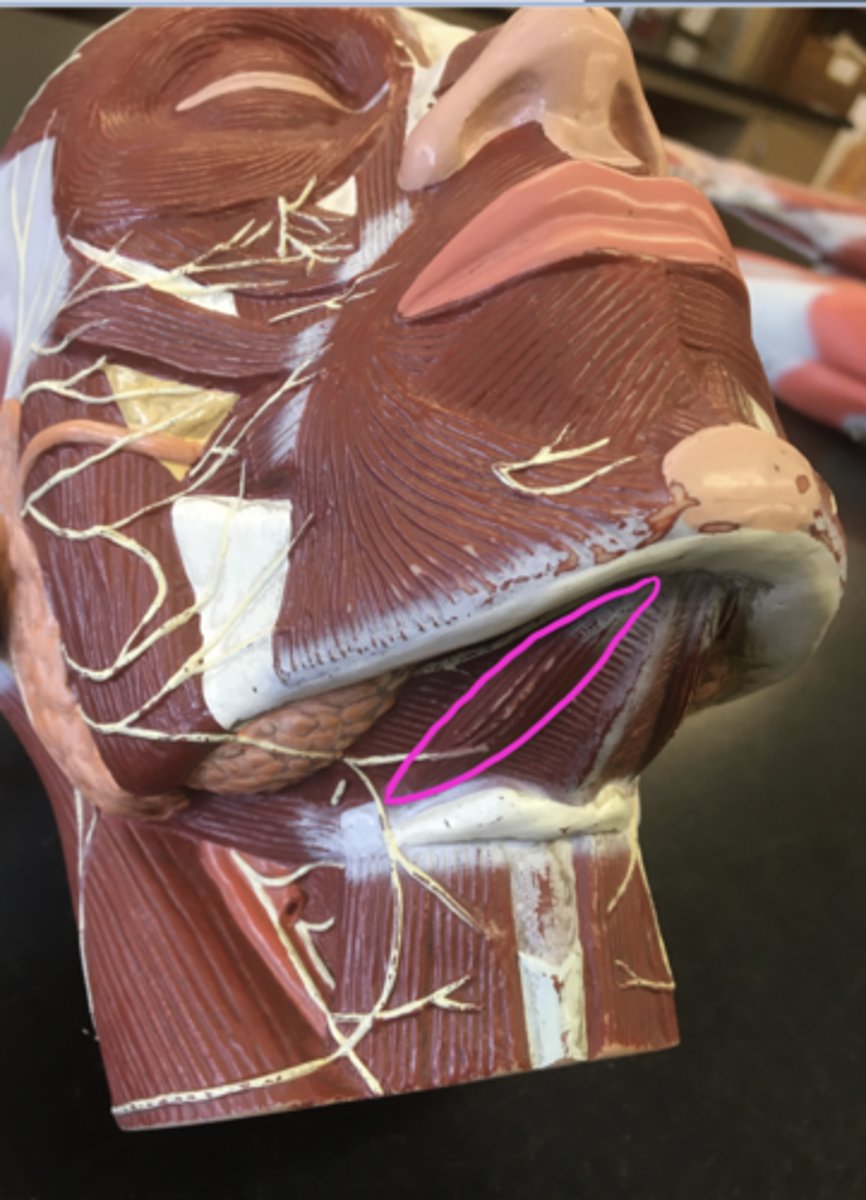

Cut to show the muscle underneath

Temporalis

Masseter

Medial Pterygoid

Lateral Pterygoid